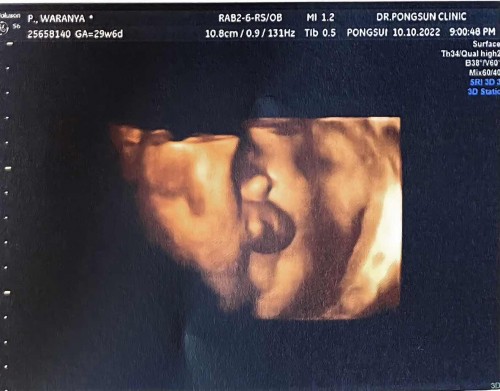

หมอบอกผมเป็นผู้ชายล้าน%😂

ทีม 18 ธ.ค.65 น้องหนัก 1663 กรัมคับ น้ำหนักลูกตามเกณฑ์ แต่น้ำหนักแม่เกินไปเยอะ🤣🤣

ชัดเจนมากค่า 😂